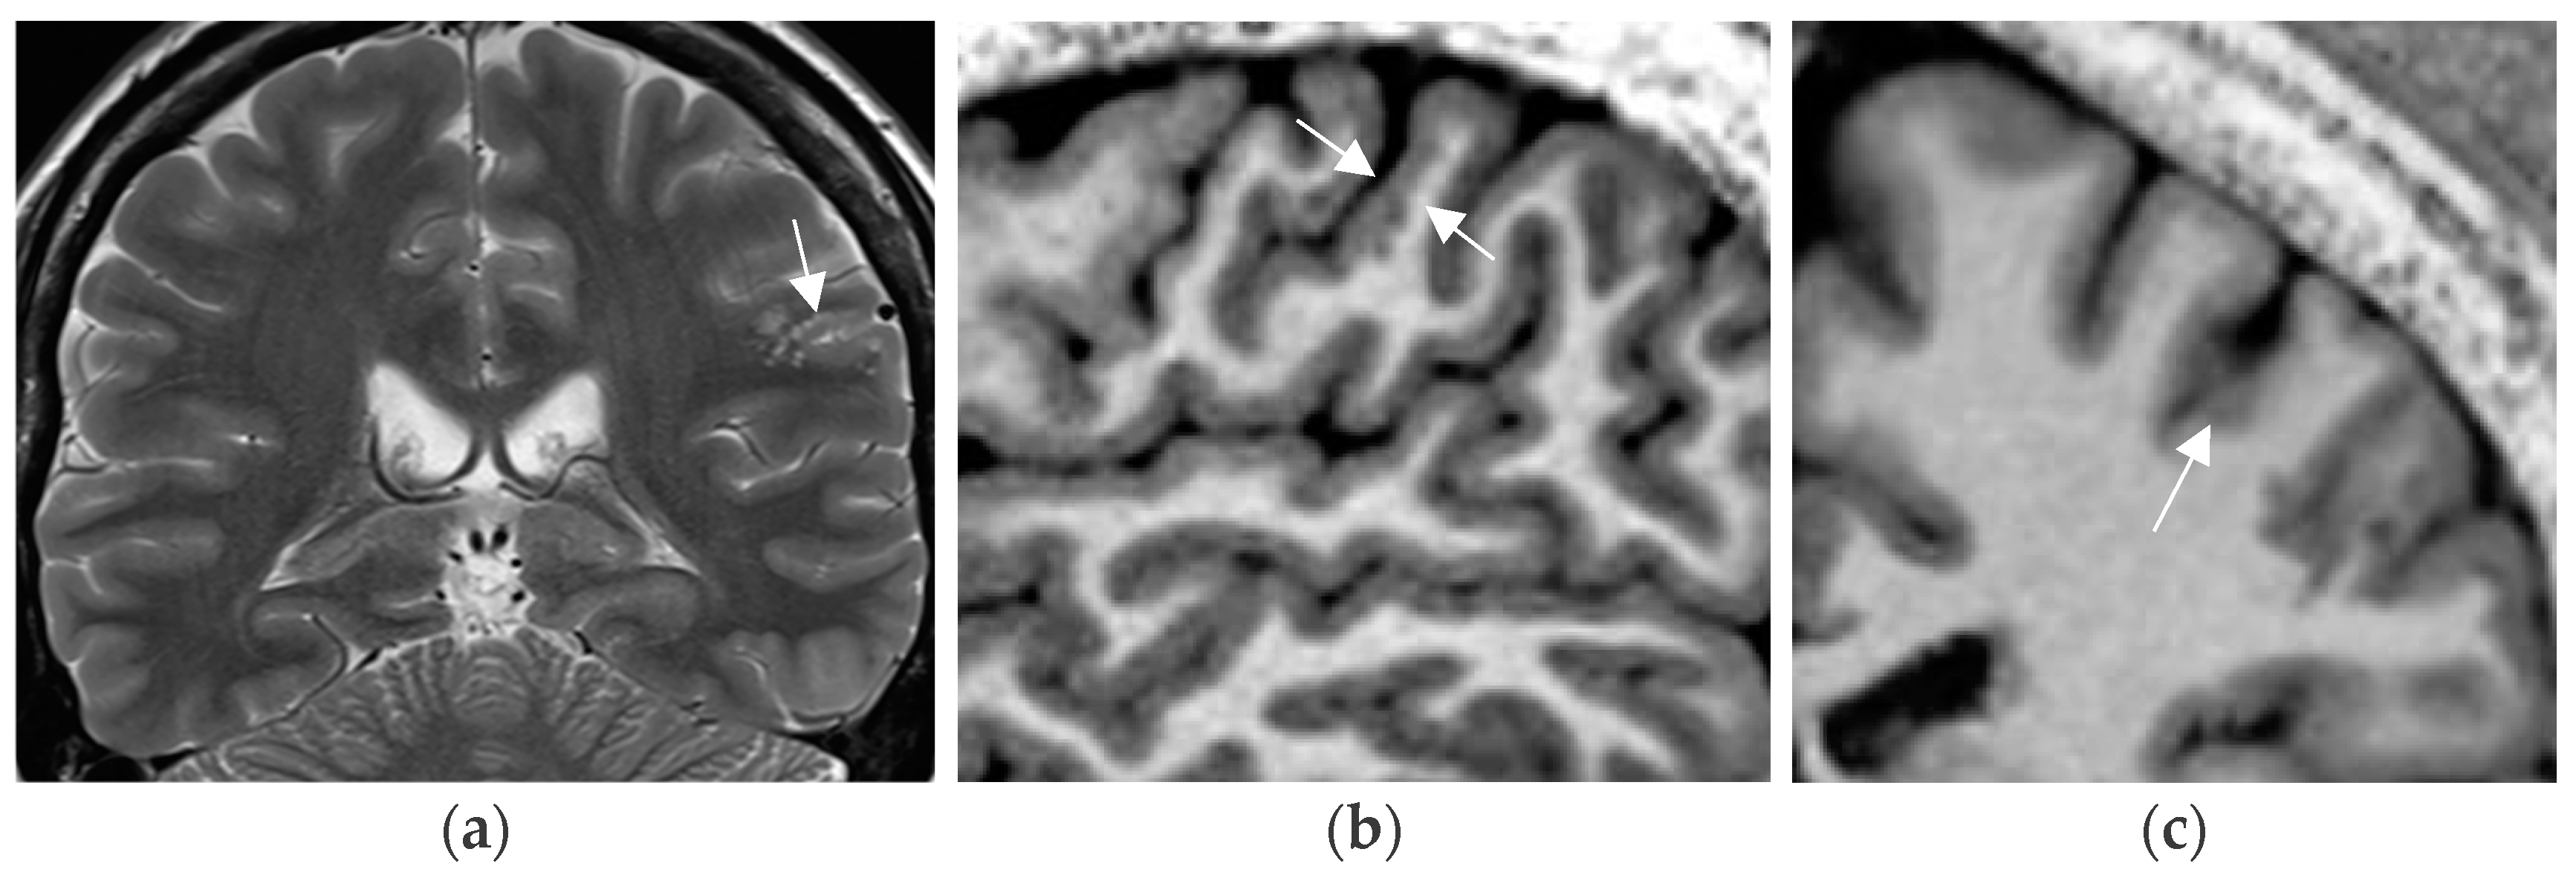

A practical tip is to increase the spatial resolution in a 3T field magnet by lowering slice thickness from 3 mm to 2–1.5 mm for T2 sequences while maintaining signal intensity. This is enabled by application of a head coil with a high number of receive coils—e.g., 64 channels in a 3T field system (Figure 3). Sensitivity for lesion detection is thus increased from 53.1% to 85.9% [72]. The most common pathologies additionally encountered in this study were FCD, nonspecific gliosis, and oligodendrogliosis.

Figure 3.

Mild malformation of cortical development along left central sulcus hardly depicted by slight cortical blurring and subcortical gliotic foci on 1.7 mm coronal T2 w image (arrow in (a)) (a). Improved visualization of the mMCD on sagittal (b) and coronal (c) MP2RAGE sequence (0.9 mm) with slight nodular irregularity of both cortical borders and focal subcortical extension (c).

Progressive substitution of 2D acquisition with 3D acquisition and thus lowering the slice thickness from 2–3 mm slice to 0.9–1 mm (=submillimetric) is a considerable yield-gaining strategy. This not only increases visual conspicuity for small lesions but moreover enables advanced postprocessing of 3D data.